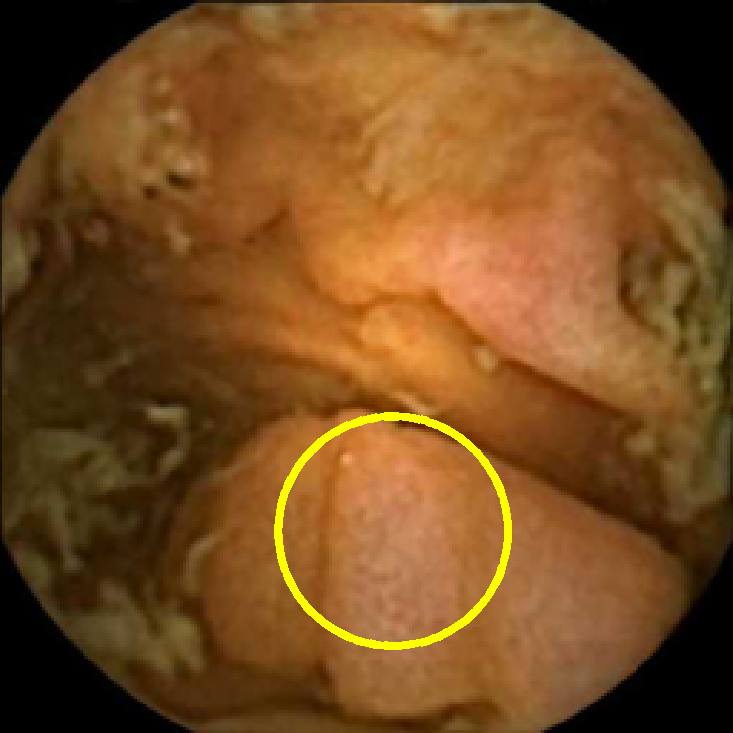

The lower bound filters out the frames with too little texture content that are unlikely to contain any polyps due to most polyps having a textured surface. The upper bound allows us to discard the frames polluted with trash and bubbles, since even if they contain polyps, they are likely to be obscured. This is illustrated in Figure 2, where we display two normal frames with low and high values of and a polyp frame with a medium value of . As expected, the first normal frame containing flat mucosa has little texture content. The second normal frame polluted with bubbles has strong texture content in the bubbles area, which is especially pronounced in the plot of . Finally, the polyp frame has moderately textured polyp area, which can also be easily observed from that has the strongest feature in that region.

In Figure 5 we show the circles of radius corresponding to the features that were correctly classified as polyps by (29). We observe that the classifier was able to identify the polyps of a variety of shapes even in the presence of small amounts of trash liquid (first row) or when the polyps are located next to mucosal folds (rows two to four in column (c)).